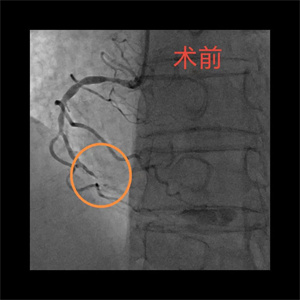

患者,李大爷(化名),76岁,因突发胸痛被家属送至我院急诊科,经完善心电图等检查后,被诊断为急性心肌梗死,随后,病人迅速被送至导管室。完善冠脉造影检查后,患者血管显影结果不容乐观,考虑左主干真性分叉合并三支病变,即右冠慢性闭塞、回旋支急性闭塞、前降支严重狭窄伴钙化。与此同时,患者出现血压、氧饱和度下降的情况,病情极其危重,随时面临死亡风险,已无法耐受及等待外科搭桥手术,急需急诊介入治疗。